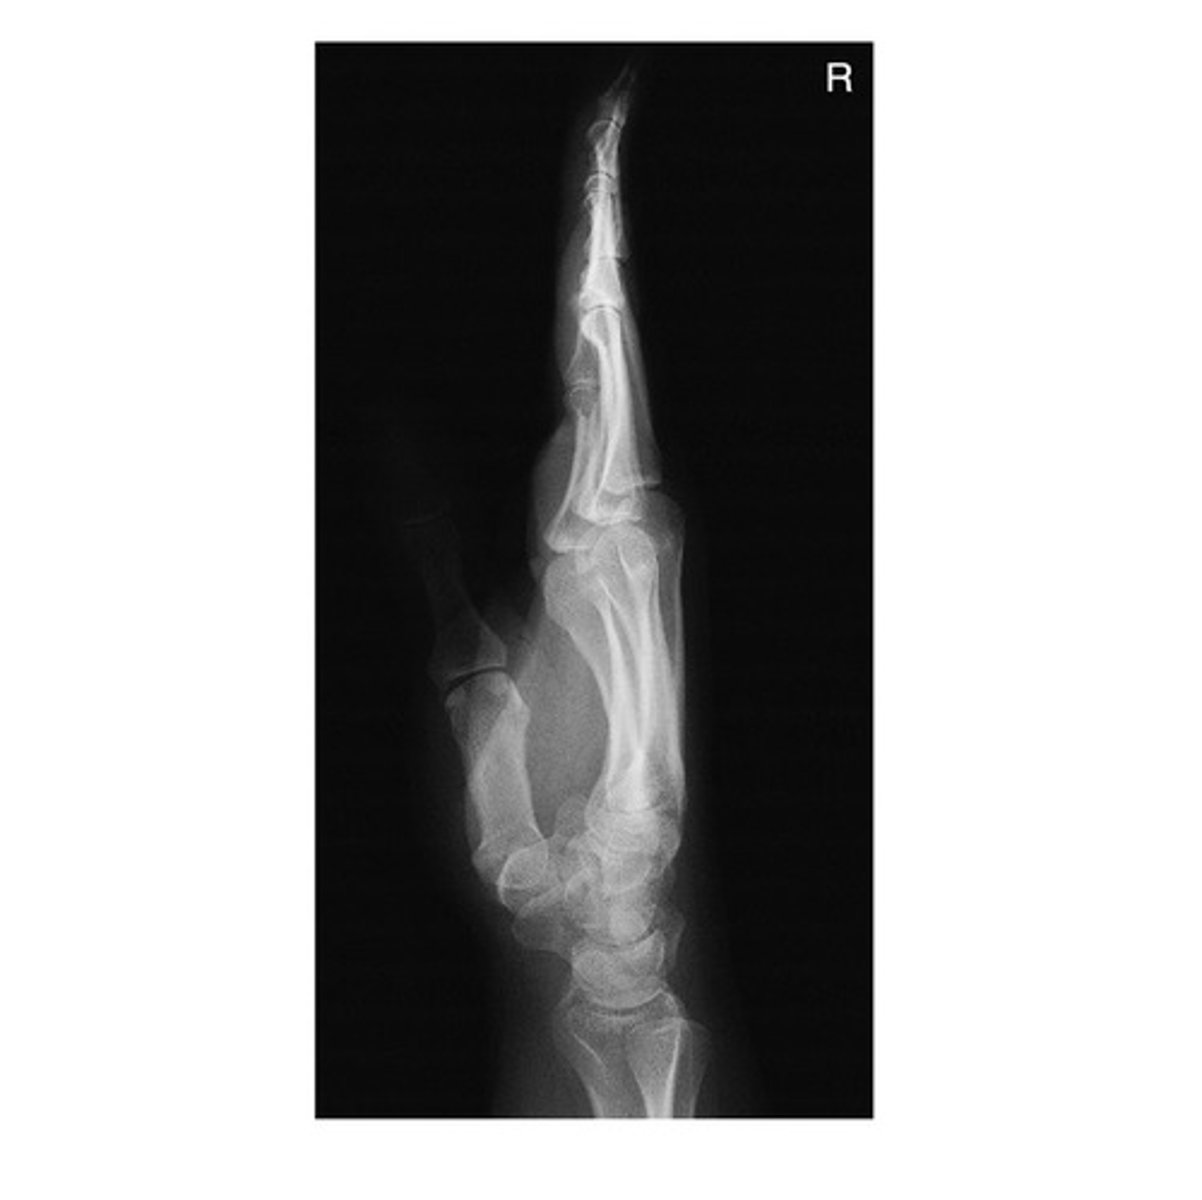

What radiographic image is demonstrated below?

a. AP Thumb

b. Oblique Thumb

c. Lateral Thumb

d. None of the above